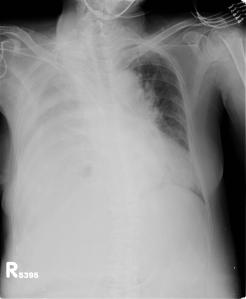

We report the case of a thymectomy performed through a subxyphoid vertical single incision port carried out in a 51 years old female myasthenic patient presenting a Masaoka stage I thymoma.

We performed extended thymectomy through a uniportal subxiphoid approach in a 51 years old female presenting a thymoma of 2.5 cm and myasthenia gravis.

Chest x-ray showing right-sided loculated effusion

CT slices, tissue window